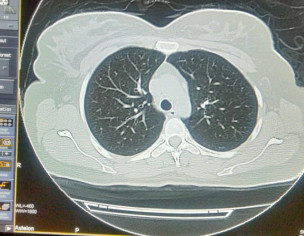

Asking for Sister, Female, 33 years old, Isl

Plz describe it. Film of hrct of corona patient

plz contact radiologist

Send full films, its incomplete